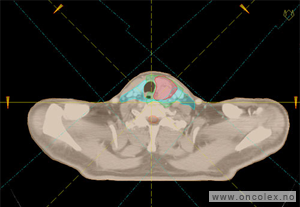

Eksempel på CT-bilder til doseplan

Hovedsvulst er markert med rødt. Risikoorganer er markert med oransje.